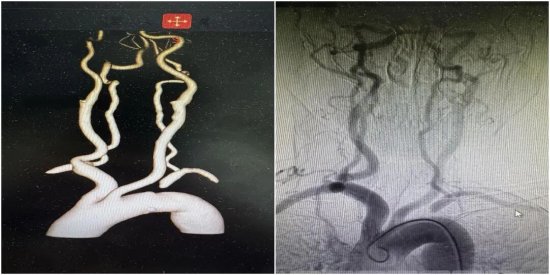

造影结果显示,张女士的闭塞病变非常坚硬,且闭塞段较长,属于复杂的“慢性完全闭塞性病变”。传统的锁骨下动脉支架植入术,通常是通过“股动脉入路”(从大腿根部穿刺)进行正向开通。然而,在手术中,当导丝尝试通过闭塞段时,遇到了巨大阻力,反复尝试均未能进入血管真腔,反而有血管夹层甚至破裂的风险。“这条路走不通,我们就得马上换一条路”。胡晓辉主任、陈刚及杨龙医生介入手术团队当机立断,决定启动备选方案—:经桡-股动脉双向“会师”技术。

(介入手术中导管“双向”会师)